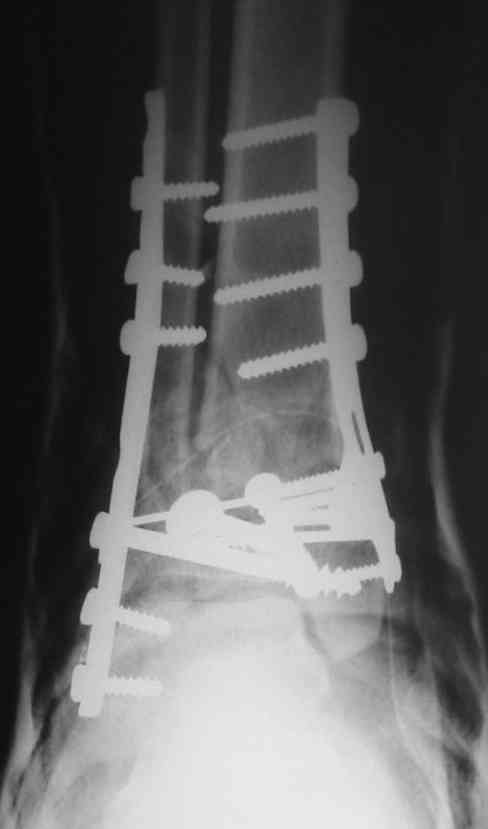

Это типичный перелом пилона, который надп лечить только открыто.Извини те что опоздал к обсуждению, но даже если вы уже оперировали больного по Илизарову это даже лучше.Посылаю картинки.

На рентгенограммах типичный перелом пилона по типу С-3. есть опыт до 100 открытых опреаций у нас в клинике. 20 примерно в год. Принцип один -все внутрисуставные переломы нуждаются в открытой репозиции и внутренней стабильной фиксации. При поступлении КТ не надо, так как получается только нагромождение костей. Истинной картины нет. Главное восстановить длину малоберцовой кости - это ключ к успеху. При поступлении меньше всего надо думать о сосудистых расстройствах, т.к. сама операция и репозиция даже сначала частичная даёт улучшение сосудитых нарушений. Причём очень быстро. Операция в 2этапа. При поступлении доступ позади наружной лодыжки, причём обязательно. После этого репозиция малоберцовой кости и фиксация пластиной 1/3 трубки под винт 3,5. Дренаж и любой аппарат наружной фиксации. Затем после спадения отёка на 5-7-10 день аппрат снимается и дугообразный разрез спереди от медиальной лодыжки 10-12 см. Главной чтобы расстояние между 1 и вторым разрезом было не меньше 7-8 см. Тогда не будет некрозов лоскутов. Таранная кость используется как матрица на неё укладываются отломки и фиксируются пицами. Ренг-контроль. Отломки лежат все отдельно, но ничего не высыпется. При переломах С-3 всегда нужна костная пластика (из крыла). Фиксация пластиной лист клевера простой или LCP. Гипс не нужен. Дренаж до 48 часов. Операция длится 3-4 часа обязательно без жгута. Посылаю примерно такой же случай.

Посылаю результат лечения предыдущего больного через год.